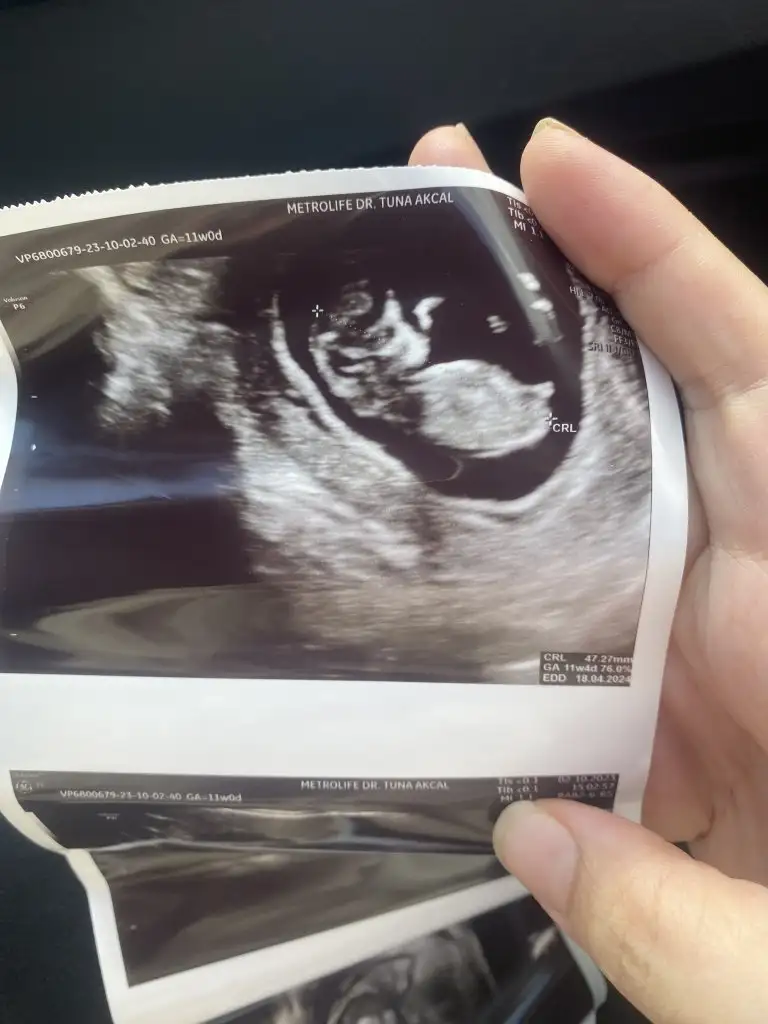

Benim bebekte pipiye benzer çıkıntı var doktor kesin erkek dedi değişir mi sizce

Şimdi şöyle ki benim kızımda 13. haftada çıkıntı gibi bir şey vardı, kordon çıktı finalde. 16. hafta altında doktorlar genelde kesin şu ya da bu demek istemiyor pek. Bekleyin biraz daha bence, çünkü parti vs yapanlar bazen üzülebiliyor :)

Merhaba arkadaslar , tam 12 haftalıkken doktora gittim 2 li tarama testi için doktor o arada cinsiyet için kemik yapısına göre erkeğe benziyor dedi.Daha sonra kanamam oldu ve daha tecrübeli bir doktora gittim o da laf arasinda %90 kız dedi 12+2 yken dedi ama 2 hafta sonra netleşir dedi. Fakat benim bebeğim geç döllenme olmuştu 6.haftada bebek ve kalp atışı duyulmamıştı 8.haftaya dogru duyulup görülmüştü sizce cinsiyeti ne olabilir kafam karıştı. Sizce geç döllenme olduğu için henüz cinsiyete dair bişey oluşmamış olabilir mi ?Benzer bir durum yaşayan varmı yada 12 haftalikken bişey söylenip değişen varmı?

12. Haftalıkken erkek dediler. 14. hafta kız. Kızım oldu.